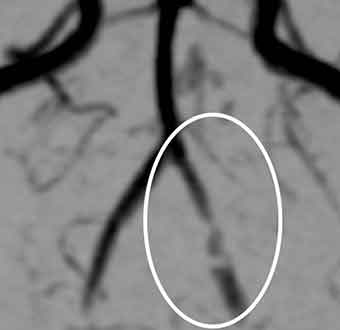

症例2. 椎骨動脈解離

40代の女性で、10代の頃から片頭痛と診断されていた方です。

ベンチプレスをしていたところ、急に後頭部の血管が切れたかのような激しい頭痛が出現。そこで、持っていたトリプタンを飲んだのですが、全く効きませんでした。そして、翌朝になっても痛みは治まらず、横浜脳神経内科を受診しました。

頭部MRA検査では、

椎骨動脈という、首から後頭部へ行く血管が変形しており、椎骨動脈解離と診断しました。

この疾患は、最悪くも膜下出血を発症して突然死をきたすこともある危険なものです。そこで、直ちに救急車で血管内治療のできる病院へ搬送していただきました。

横浜脳神経内科の症例経験では、筋トレ頭痛の原因の多くは可逆性脳血管攣縮症候群です。しかし、まれにこうした危険な疾患の場合もあります。さらに、椎骨動脈解離の詳しい病態については、専門家の記載6)をご参照ください。